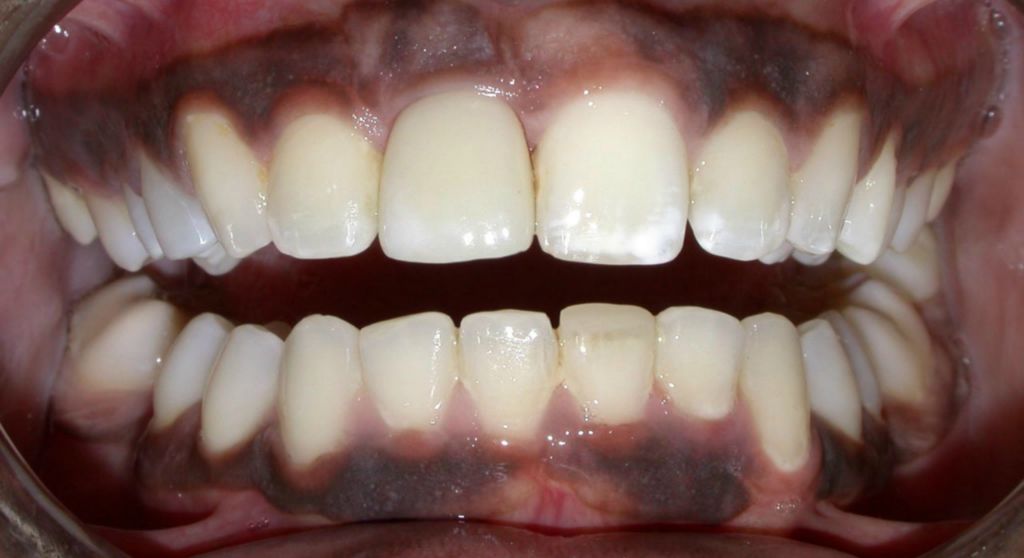

After